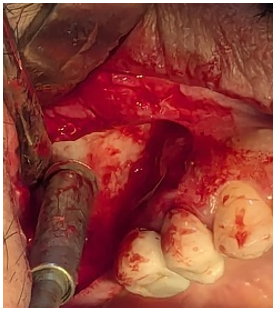

Surgical procedures were done under local anesthesia, a palatal incision just below the top of the alveolar crest with vertical releasing incisions was made, and a mucoperiosteal flap was raised to expose the alveolar crest and the lateral aspect of the maxilla (figure 2).

Autogenous bone can be collected with a bone scraper to collect the bone and thinning the lateral maxillary wall simultaneously (Figure 3). A disk bur with slow speed handpiece was used for further bone osteotomy of the lateral wall until sinus shadow appears to the operator, at this stage operator should stop using the rotary bur (figure 4).

Figure 2: A full-thickness flap is reflected to expose the bone up to the zygomatic buttress. A vertical incision is placed distal to the canine, and a horizontal incision is made toward the palatal aspect of the ridge crest

Figure 3: Autogenous bone is harvested from the lateral wall of the sinus using a bone scraper and mixed with synthetic bone particles. The bone scraper also thins the lateral wall of the sinus

Figure 4: A circular bone osteotomy is performed on the lateral wall until the maxillary sinus shadow appears. Rotary bur osteotomy is stopped at this point to avoid over-thinning the lateral wall